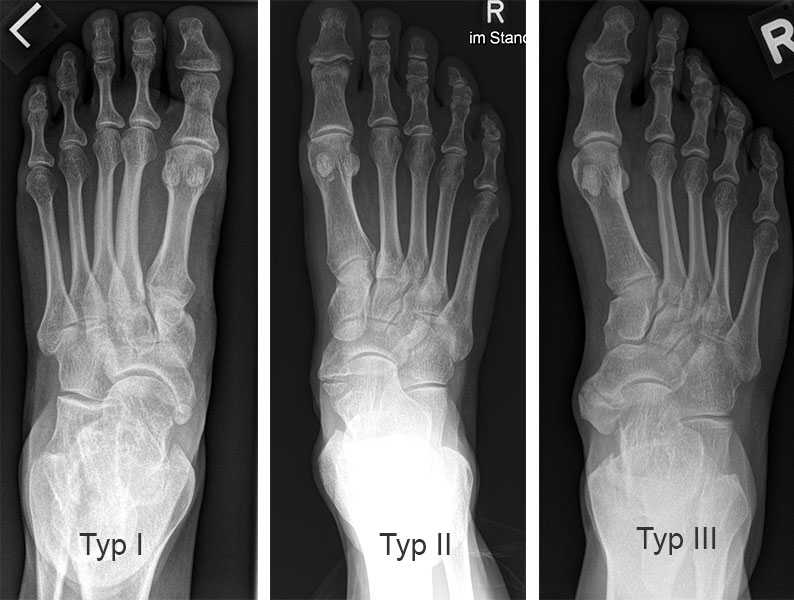

Radiologische Einteilung (Abb. 2)2:

Typ I: Ovalär bis rundliches, glatt begrenzter akzessorischer Knochen im Sehnenansatz des musculus tibialis posterior liegt.

Typ II: Trianguläres Ossikel, welches eine knorpelige Verbendung (Synchondrose) zum Os navicularis pedis hat. Typ II ist die häufigste Variante 2.

Typ III: Nach medial erweitertes Os naviculare im Sinne eines Os naviculare cornutum (entspricht einem fusioniertem Typ II).